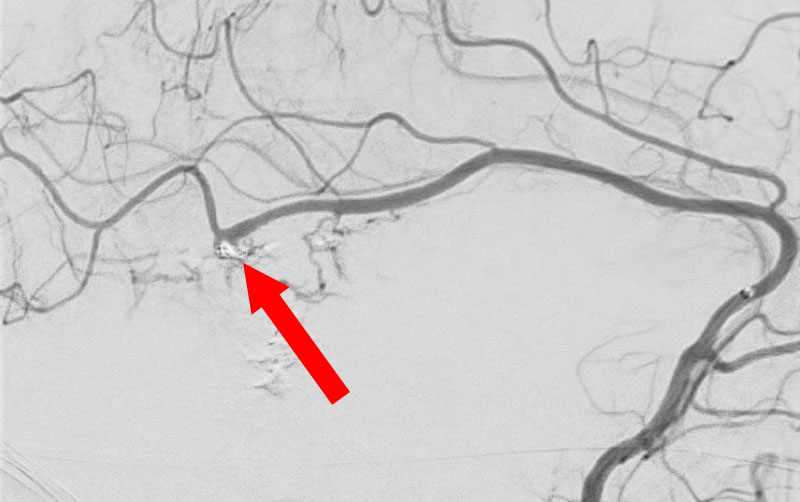

'25年10月

脳動静脈奇形

60代

大阪府の病院

No.1583 手術前

No.1583 手術中

No.1583 手術後